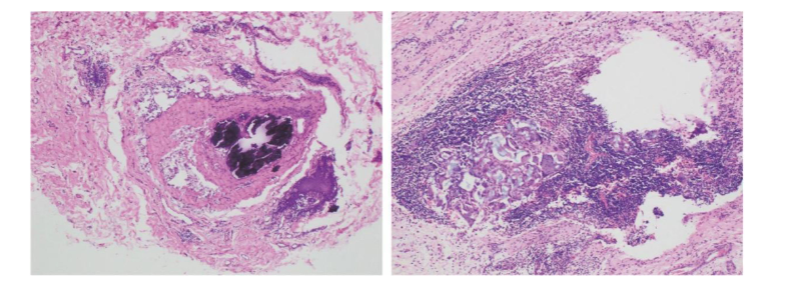

行超声引导下空芯针穿刺活检证实为非特殊类型浸润性乳腺癌,WHO分级为2级(总评分为6/9:腺管形成3分,核异型性2分,核分裂活性1分)。免疫组织化学分析显示ER和PR表达缺失,40%的肿瘤细胞雄激素受体(AR)呈弱至中度阳性,HER2强阳性(3+),Ki-67增殖指数为25%。

1.png图1.诊断性空芯针穿刺活检的基线免疫组织化学结果(×200):(A)雌激素受体染色显示阳性细胞核比例<1%(雌激素受体阴性);(B)人表皮生长因子受体2(HER2)染色显示>10%的肿瘤细胞呈均匀、强阳性(3+)膜反应性,证实HER2过表达。

超声引导下同侧腋窝淋巴结细针穿刺活检显示继发性非特殊类型癌,受体状态相似(ER 3% ±,PR-,HER2 3+,Ki-67 25%)。右锁骨上淋巴结细胞学检查显示簇状多形性恶性细胞,符合转移癌特征。